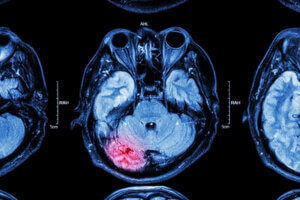

Severe Traumatic Brain Injury

Severe traumatic brain injuries result in a loss of consciousness of more than 6 hours and a Glasgow Coma Scale of 3 to 8. The Glasgow Coma Scale is the most common method of describing the level of consciousness in a person who has suffered a traumatic brain injury.

Very Severe Brain Damage

By ‘very severe’, we mean that the victim’s brain damage is so acute that they are left with serious physical and mental disabilities. The injured person will be required to adapt to a new way of living. The effects of severe brain injuries are also felt acutely by the victims’ families, and their lives will change drastically.